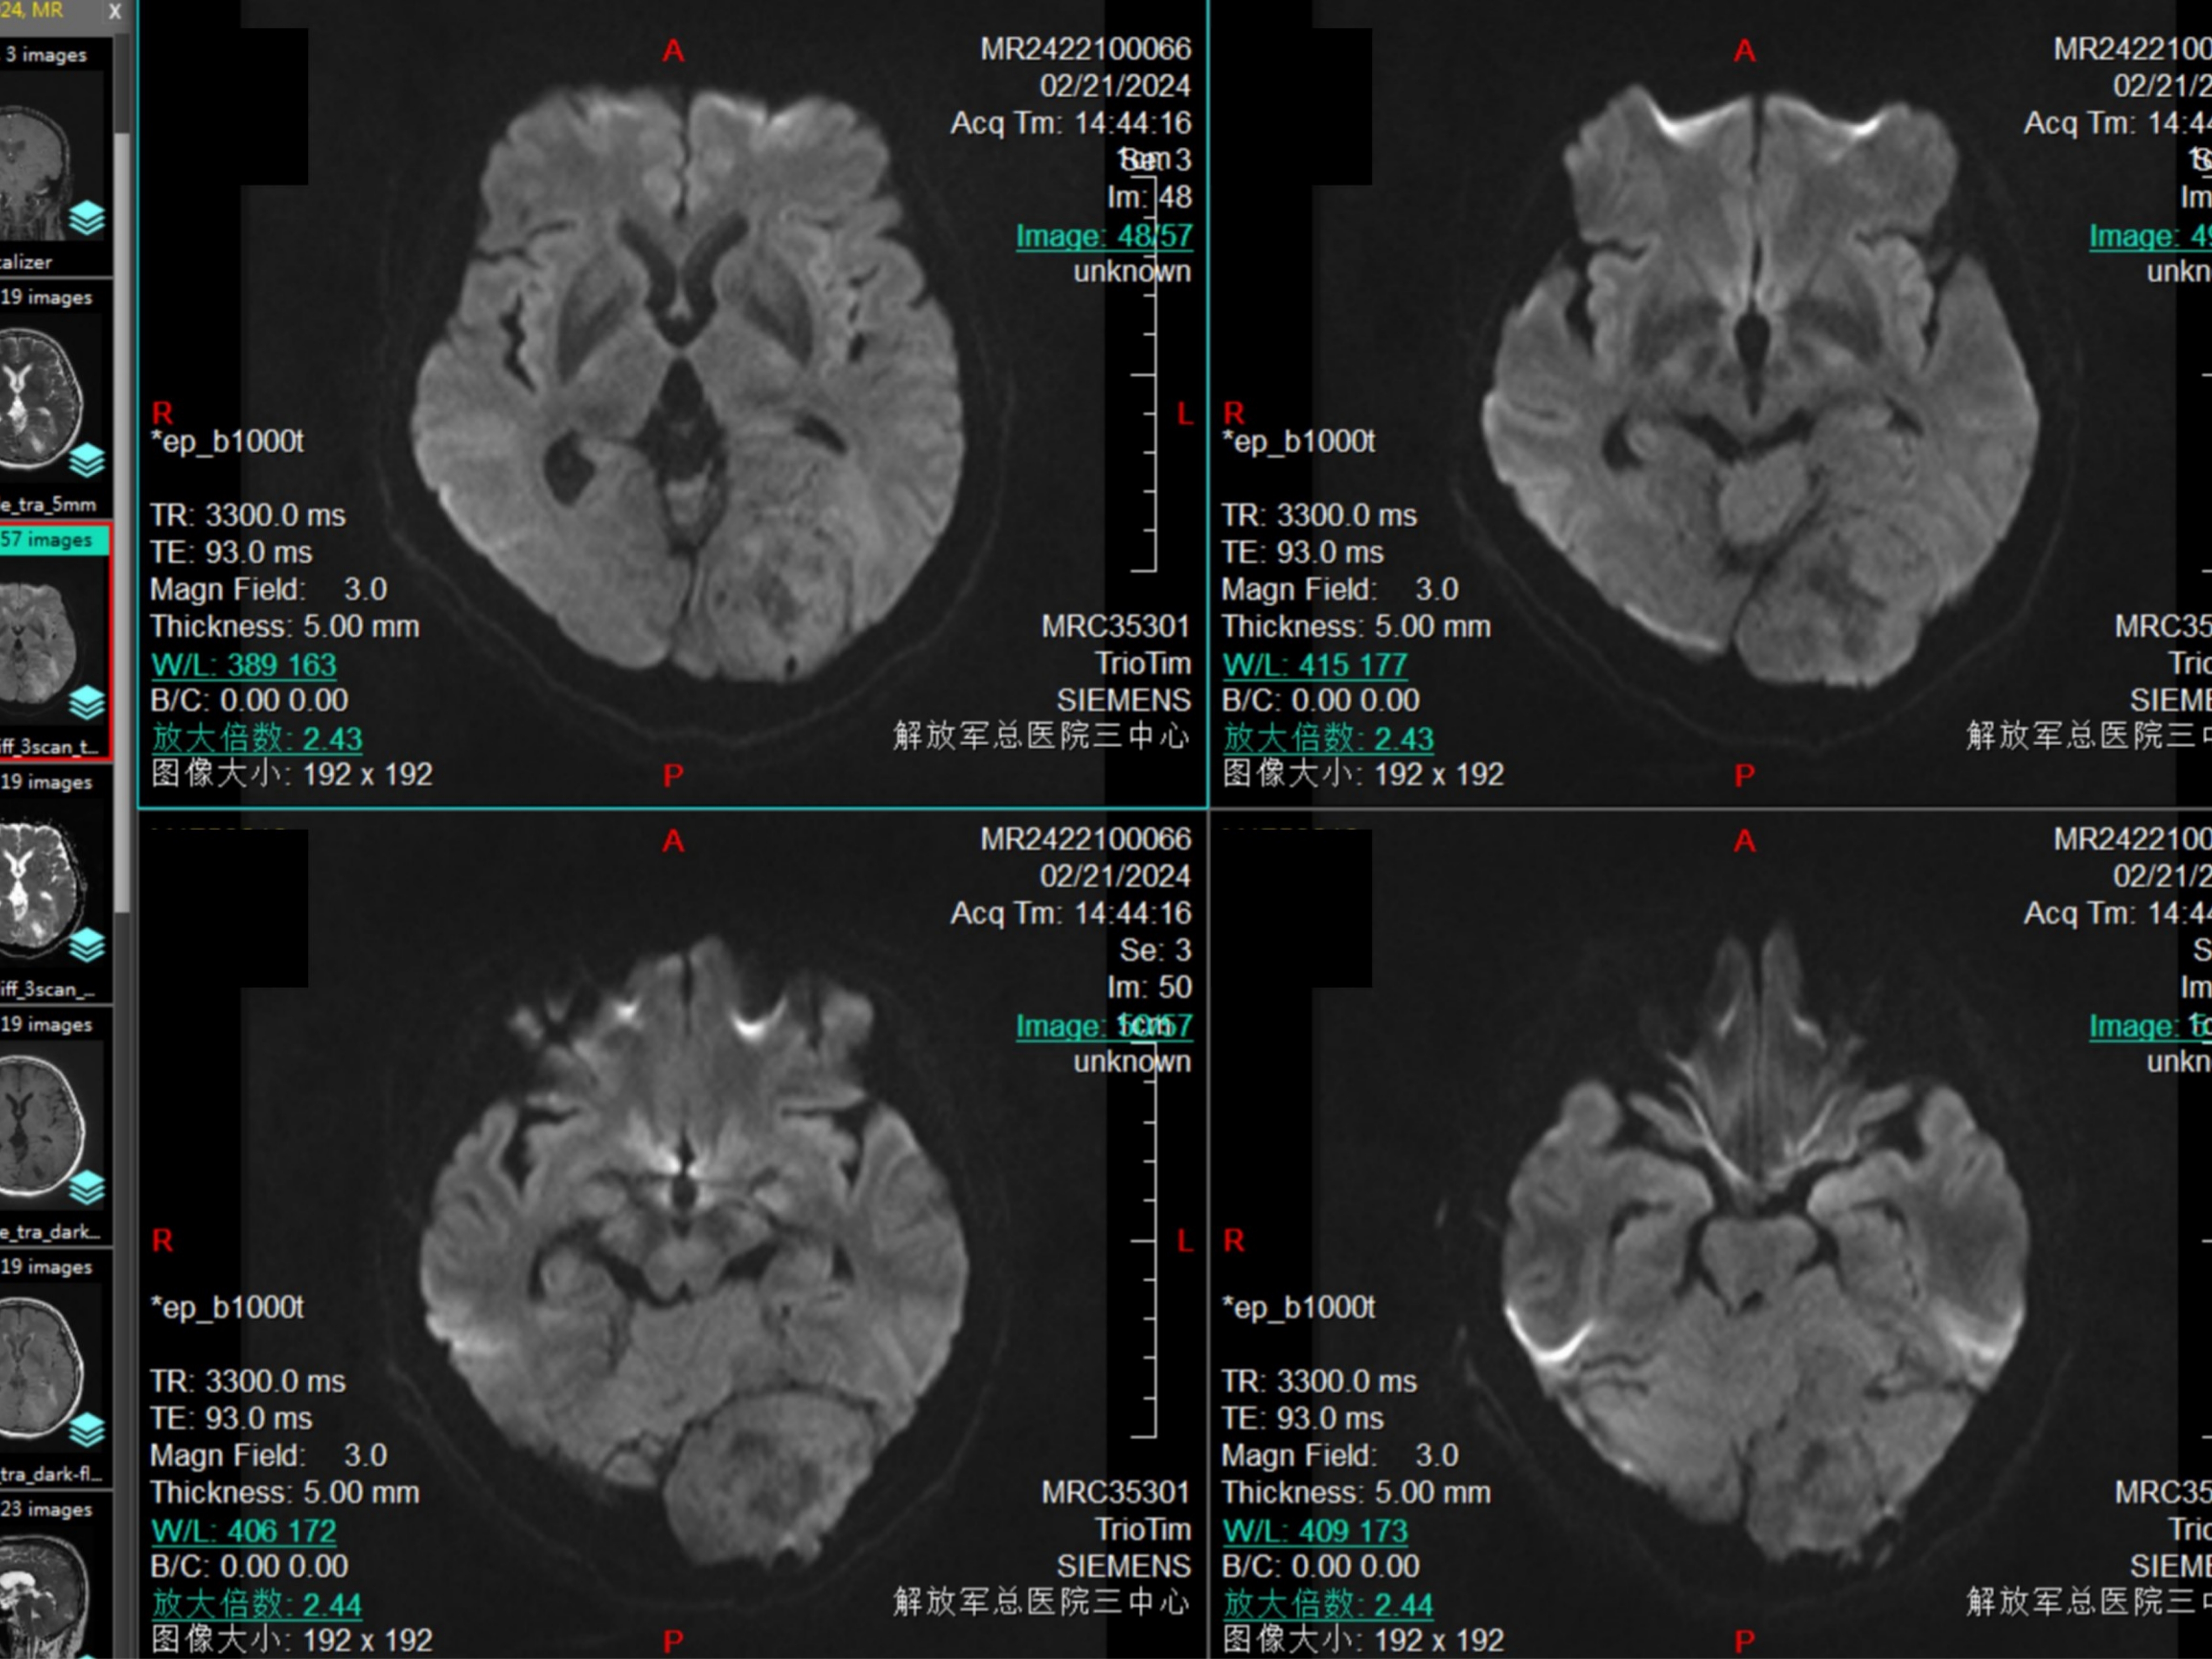

DWI为等信号,有黑色现状结构,考虑为膨胀性生长的小脑幕结构。